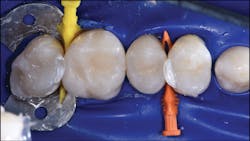

Two key components for tight contacts are wedges and separators; in the case of the Biofit Posterior Matrix System (Bioclear Matrix), the Diamond Wedge and the Twin Ring Separator are used. It is important to use a wedge with a low profile, which provides a gingival seal without distortion of the matrix. Additionally, the separator should be able to provide strong separation and help to seal the matrix along the gingival line angles.

In the following case study (figures 1–11), the techniques and methods discussed will be demonstrated with the treatment of a quadrant of four posterior restorations. Four interproximal smooth-surface carious lesions are conservatively treated with two nonretentive saucer preparations and two marginal ridge-preserving opportunistic preparations.